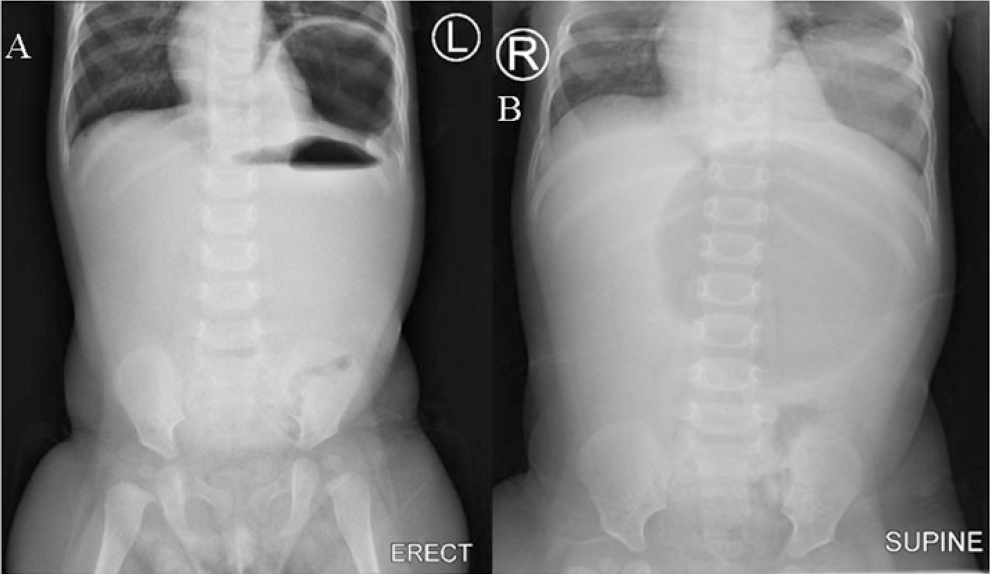

Methods: We present a six-month female baby who presented with clinical features of intestinal obstruction. Ultrasonography of the abdomen revealed gastric volvulus. The baby underwent emergency laparotomy. Gastric volvulus with splenic herniation was encountered through a diaphragmatic hernia.